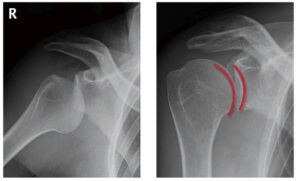

| 病態 | 直接肩をぶつける、または腕を引っ張られることで、上肢に伸展・外転・外旋が強制され肩が後に持っていかれるような動作の時に生じる。95%以上が前方脱臼で、周囲の靱帯が伸びるため一度脱臼すると反復性脱臼になりやすい(20歳未満の初回脱臼では約90%が反復性となる)。合併症として、肩関節脱臼では上腕骨頭が関節窩から擦れながらはずれ、互いに傷つき骨折することが多く、上腕骨頭に陥没ができるのがHill-sachs lesion、関節窩の縁に骨折を認めるのがBankart lesionという、しかし、緊急性は低い。また、中高年では腱板断裂を合併することも多い。 |

| 検査 | 【身体所見】 apprehension test:肩関節外転外旋位で水平外転し肩がはずれそうな不安感で陽性 【画像検査】 ①X線:左右の肩の画像を撮像、正常は上腕骨頭と関節窩が赤線のように適合している(右)が、脱臼すると適合が見られない(左) ②CT:Hill-sachs lesion、Bankart lesionの評価 ③MRI:関節唇や腱板などの軟部組織の損傷の評価、occult fractureの評価 |